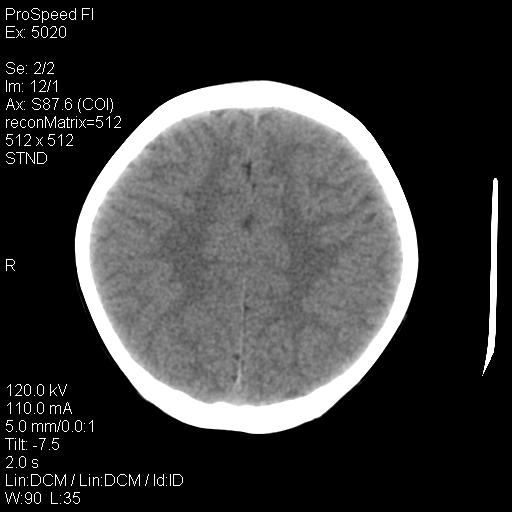

标题: PED1637:M 6Y 顶部无痛性包块两月。 [打印本页]

标题: PED1637:M 6Y 顶部无痛性包块两月。

2、颅骨局部缺失,边缘光滑、整齐

颅骨的病损表现为内外颅骨板层不规则的锋利的破坏,形成“斜边缘”,有一定的特点

颅骨为好发部位,生长缓慢,常位于顶骨、枕骨及颞骨,表现为颅骨缺损,呈圆形或椭圆形,边界清,无硬化

事发冠状缝与矢状缝交界区,密度较低,考虑表皮样囊肿可能性大,其次不除外嗜酸性肉芽肿